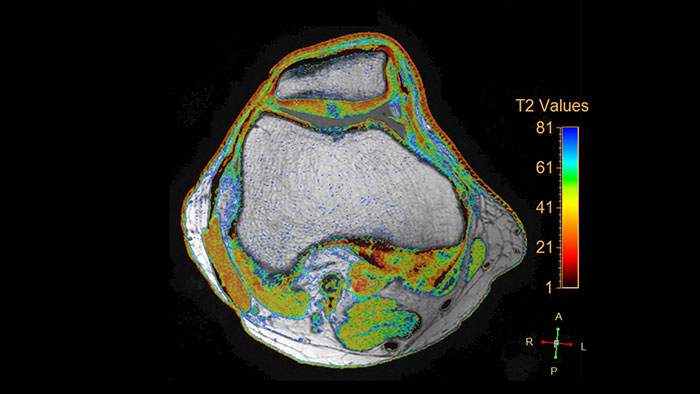

MR Cartilage Assessment

Visualize cartilage structures

Enables the visualization of cartilage structures integrated with color-coded T2 maps. Positioning of cartilage-shaped, layered region of interest is used to assess variation of T2 values across the cartilage depth to determine the degradation of the cartilage.

Benefits

- The MR Cartilage Assessment application features a task-guided workflow for the quantitative analysis of T2 relaxation time to support cartilage assessment and disease status.

- The application provides segmentation tools, allowing measurements of cartilage layers and segments.

- T2 values are numerically and graphically displayed per layer and segment.